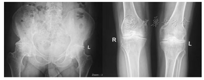

患者,女,49岁,体质量69 kg,体质量指数(BMI)25.8 kg/m2,因"双下肢活动受限,双髋、双膝部疼痛21年,并进行性加重半年"入院,患者28岁时出现无明显诱因的双下肢活动障碍,双髋、双膝部肿痛,就诊于当地医院,行相关检查后诊断为"血友病A型",给予补充凝血Ⅷ因子制剂,症状明显好转,此后反复出现全身多关节肿痛,每次均给予补充凝血Ⅷ因子制剂。1年前当地医院检查抗-HCV(+),近半年来感双髋、双膝部疼痛,活动受限,以右侧为著,并进行性加重,于2018年8月7日收住我院骨科。根据病史、症状、体征及实验室检查,诊断为:血友病A型;血友病性关节炎;丙型肝炎。专科查体:左侧髋关节活动内收15°、外展20°、外旋10°、内旋15°、屈曲90°;右髋关节活动内收、外展各10°、内外旋各5°、屈曲70°,右下肢呈屈曲、外旋畸形位,双膝关节屈曲障碍。实验室检查:(1)术前出凝血:凝血酶原时间(prothrombin time,PT)11.5 s,活化部分凝血活酶时间(activated partial thromboplastin time, APTT)107.6 s,凝血Ⅷ因子活性(FⅧ:C):2.5%;(2)凝血Ⅷ因子活性+APTT纠正试验:APTT(患者)103.0 s,APTT(正常)31.4 s,APTT(混合)37.5 s,APTT(1 h)40.6 s,APTT(2 h)42.4 s;(3)术前感染八项:抗-HCV(+),HCV-RNA3.38×107 IU/ml。影像学检查:双下肢不等长,右侧771 mm、左侧784 mm,右侧股骨头形态失常,局部骨质密度增高,双侧股骨外上髁变尖,双膝关节面不光整,关节间隙狭窄,双踝关节面粗糙,右侧股骨头形态失常,局部骨密度增高,腔隙狭窄;双侧髋关节、膝关节、踝关节骨关节病。

临床诊断为血友病性关节炎,双髋及双膝关节均有关节置换适应证,但右侧髋、膝关节病变较左侧严重,在完善相关检查,无心肺等手术禁忌证后,于全麻下行"右侧全髋关节置换术+右侧全膝关节置换术"。术前3 d静脉输注凝血Ⅷ因子2 000 IU/次,每12小时输注1次;术前2 h静脉输注凝血Ⅷ因子3 000 IU,术前30 min急查PT13.8 s,APTT 31.3 s,凝血Ⅷ因子活性(FⅧ:C)108.6%;术前30 min静脉输注联合术中局部应用氨甲环酸减少出血及输血,术中动态监测凝血Ⅷ因子活性保持在80%以上,术中出血900 ml,输全血600 ml。术后持续监测凝血Ⅷ因子活性,按需输注凝血Ⅷ因子,同时给予抗感染、止血、止痛等对症治疗。术后第32天影像学检查提示右侧人工髋、膝关节位置正常,关节对位良好,结构完整。手术前后影像学检查见图1、图2。术后第34天出院。